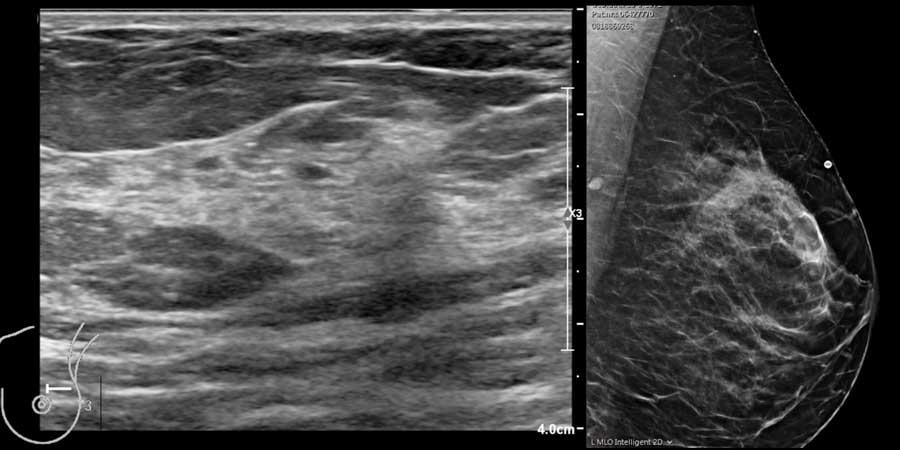

Đây là hình ảnh siêu âm bình thường của tuyến vú.

Lớp xám phía trên là da.

Tiếp theo là sự pha trộn giữa mô mỡ (tối hoặc giảm âm) và mô tuyến (xám sáng hoặc tăng âm).

Lớp có vân sọc phía sau mô vú là cơ ngực.

Phía sau hoặc sâu hơn so với xương sườn có một vùng đen hay bóng cản âm phía sau.

Phổi là lớp có thể quan sát sâu nhất.

Không khí trong phổi phản xạ hầu hết sóng âm, tạo ra một đường sáng hoặc tăng âm với bóng cản bẩn phía sau.

Thành phần mô vú

Siêu âm cho phép xác định thành phần mô vú: mô xơ tuyến đồng nhất – mô không đồng nhất – hoặc mô mỡ đồng nhất (hình).

Lưu ý rằng hình ảnh nhũ ảnh và siêu âm rất tương đồng nhau.